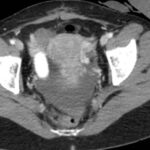

Tomografía de abdomen y pelvis con cte ev: del 13/10/2023.

Complicaciones posquirúrgicas

Tomografía de abdomen con cte ev: del 20/10/2023.

Tomografía de abdomen con cte ev: del 26/10/2023.